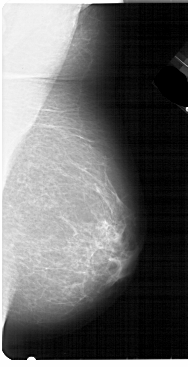

A_1948_1.RIGHT_MLO

RIGHT_MLO LINES 5491 PIXELS_PER_LINE 2806 BITS_PER_PIXEL 12 RESOLUTION 43.5 NON_OVERLAY